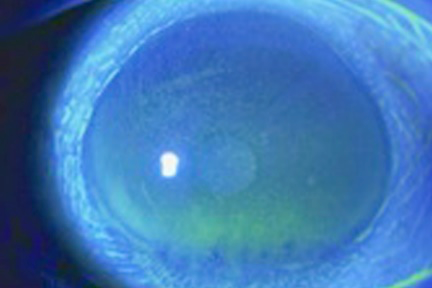

01.細隙灯顕微鏡による角膜・結膜の観察

涙液の溜まり具合(瞼の縁と角膜表面にたまる涙液層の高さ)を調べます。

02.フルオレスセイン液で表面を染めて、角膜や結膜に傷がないか調べます。

03.涙液層破壊時間測定(BUT)

フルオレスセイン液で角膜表面を染色し、涙液層が何秒で破たんするか調べます。